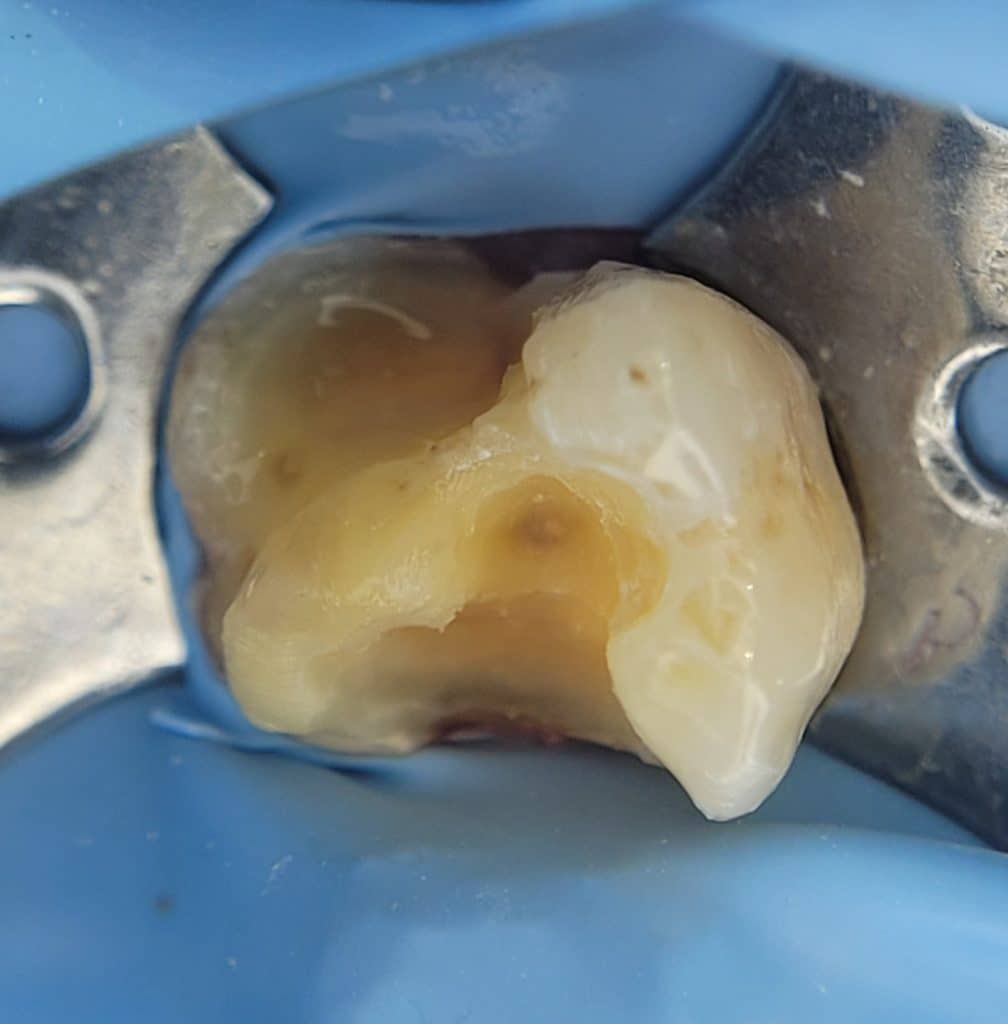

27 numarali diste derin çürük biraz temizlendikten sonra çürük boyası ile kontrol edip etkilenmiş dentini de temizledik

Mezialde pulpa ekspoze oldu ultradent mta flow ile pulpa kaplaması yaptık. Sonrasında hemen kuraray clearfil se bond ile immediat dentin sealing, Üzerini gc ever x flow ile resin coating yapıp. Mezial ve distal marjinleri inşa etmeye başladık. Yan duvarlar hazirlandiktan sonra incremental yöntemle kaybedilen dentin dokusunun yerinde ever x posterior kullandık. Burası da bitince gc ganniel ile kaybedilen mineyi oluşturduk, okluzalde tuberkuller fissurleri oluşturup restorasyonumuzu bitirdik .